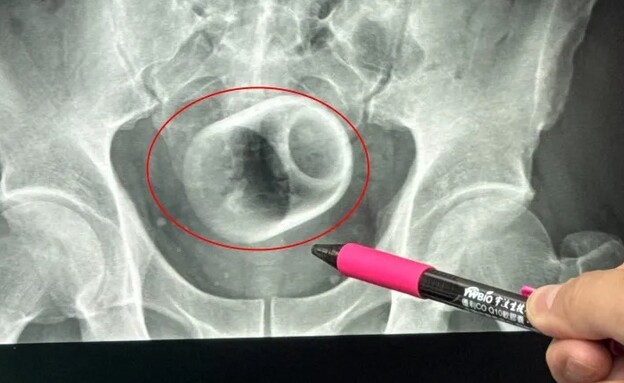

גבר במשקל 270 ק"ג חולץ מדירתו באמצעות מנוף